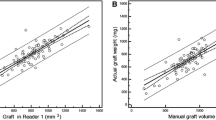

Major hepatectomy causes a risk of postoperative liver dysfunction, failure, and infections like surgical site infection. Preoperative assessment of the liver volume and function of the remnant liver is a mandatory prerequisite before performing such surgery. The aim of this work is to develop and test a software application for evaluation of the residual function of the liver prior to the intervention of the surgeons. For this purpose, a technique for evaluation of liver volume from computed tomography (CT) images has been developed. Furthermore, the methodology algorithms were implemented and incorporated within a software tool with three basic functionalities: volume determination based on segmentation of liver from CT images, virtual tumour resection and estimation of the residual liver function and 3D visualisation. Forty-one sets of abdominal CT images consisting of different number of tomographic slice images were used to test and evaluate the proposed approach. Volumes that were obtained after manual tracing by two surgeon experts showed a relative difference of 3.5 %. The suggested methodology was encapsulated within an application with user-friendly interface that allows surgeons interactively to perform virtual tumour resection, to evaluate the relative residual liver and render the final result. Thereby, it is a tool in the surgeons’ hands that significantly facilitates their duties, saves time, and allows them to objectively evaluate the situation and take the right decisions. At the same time, the tool appears to be appropriate educational instrument for virtual training of young surgeon specialists.